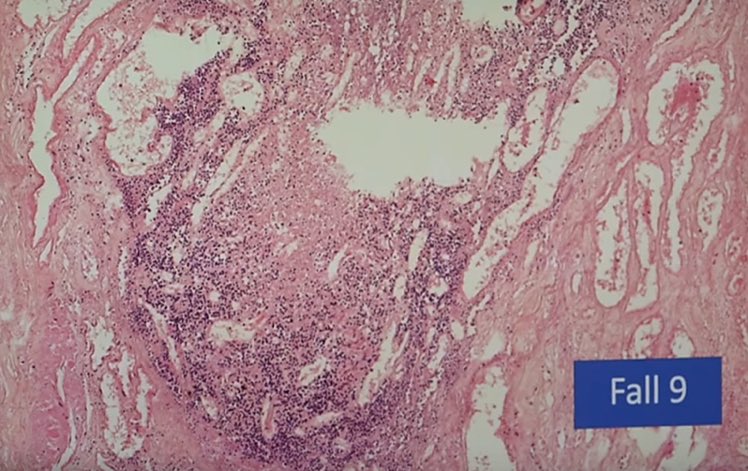

النتائج الرئيسية:

التهاب عضلة القلب اللمفاوي ، التهاب غشاء القلب ، التهاب التامور ، "غلبة الخلايا الليمفاوية" :

⁃نموذجي للعدوى الفيروسية

⁃يصعب التعرف عليها بالميكروسكوب ،

⁃غالبًا ما يُساء تفسيرها من الناحية النسيجية على أنها معدية (الخلايا الحبيبية!). 6️⃣

⁃عادةً ما تكون البؤر صغيرة متعددة ، وبالتالي لا يتم اكتشافها في كثير من الأحيان

⁃التأثير على قدرة الضخ (تحذير: وزن القلب الحرج)

⁃فشل القلب في الجهاز عندما يتأثر نظام التوصيل ؛ "الموت القلبي المفاجئ" ، الاكتشاف بالكاد ممكن (حوالي 15000 قسم)7️⃣